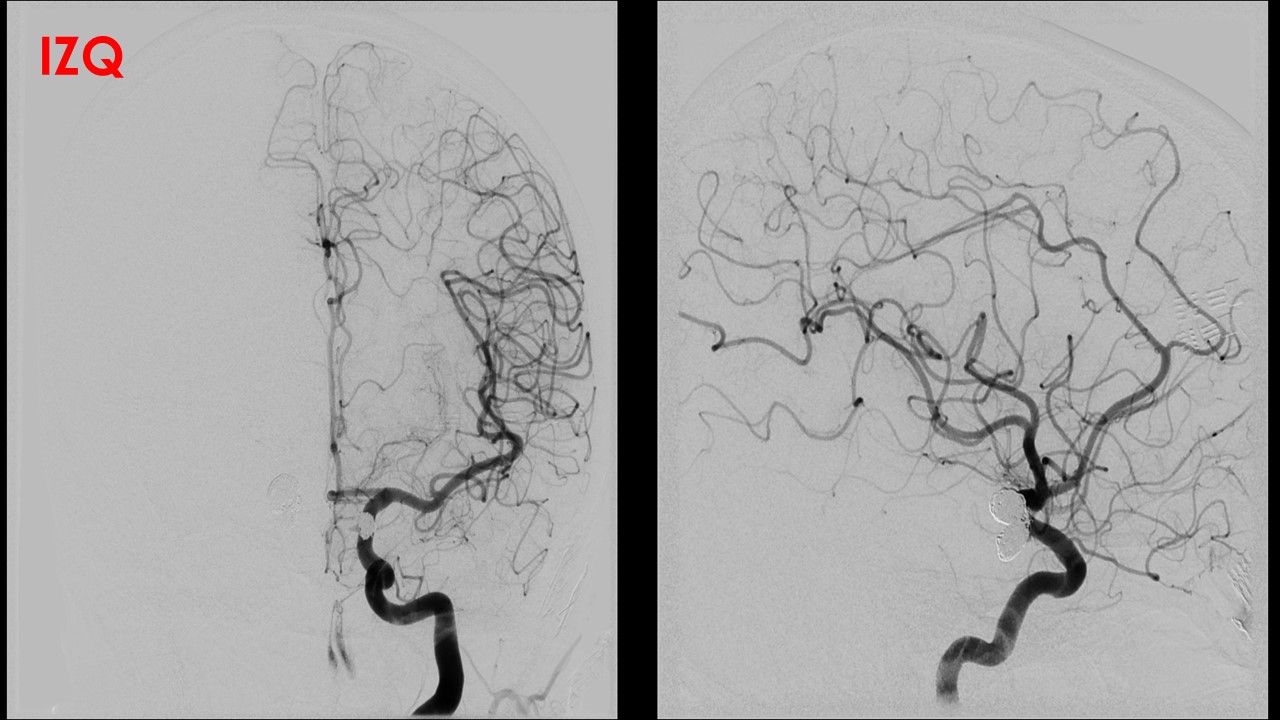

Procedimiento: Se realiza estudio diagnóstico confirmando la presencia de dos aneurismas localizado en

origen de comunicantes posteriores:

El derecho de 11x9x8mm con cuello de 5.3mm de morfología polilobulada, en su componente inferior se

origina la comunicante posterior.

El izquierdo de 6.6×4.5×6 con cuello de 3.12, comprometiendo el origen de comunicante posterior.

Se realiza microcateterismo selectivo del saco aneurismático derecho, con protección de balón Transform,

el cual se ubica en carótida previo a la bifurcación, posteriormente se dispone en su interior un total de 15

coils. En la serie angiográfica de comprobación se identifica persistencia de mínimo saco residual con

permeabilidad de la comunicante.

En un segundo tiempo se realiza microcateterismo selectivo del saco aneurismático izquierdo, con

protección de balón Transform, el cual se ubica en carótida previo a la bifurcación, posteriormente se

dispone en su interior un total de 9 coils. En la serie angiográfica de comprobación se identifica

persistencia de mínimo saco residual y ausencia de permeabilidad de comunicante posterior, pero con

adecuada permeabilidad de ACPI desde basilar.